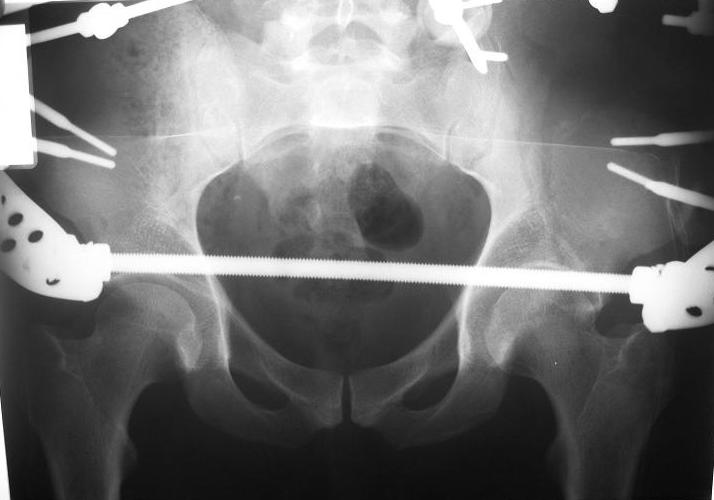

Поступил пациент после кататравмы (упал с высоты 4м). После обследования установлен Ds: Сочетанная травма. ЗТГК перелом 5-6 ребер справа. Ушиб левого леогкого. Оскольчатый перелом крыла подвздошной кости слева, со смещением. в экстренном порядке выполнена операция о/синтез таза стержневым аппаратом. Снимки прилагаются. Пациент со 2-го дня стал ходить без костылей. Из анамнеза жизни у пациента имеется гепатит В и С, с 1998г. употребляет наркотики (героин 1г в день нормальная доза). На контрольных снимках таза в аппарате смещение отломков сохраняется, да еще и стержни сломались. Подскажите ув.коллеги, как поступить в данной ситуации: оставить все как есть или добиваться репозиции в аппарате, или планировать на открытую репозицию. На сегодняшний день пациент стабилен, по анализам компенсирован. Принимает героин по другому справиться не может. С ув. Андрей